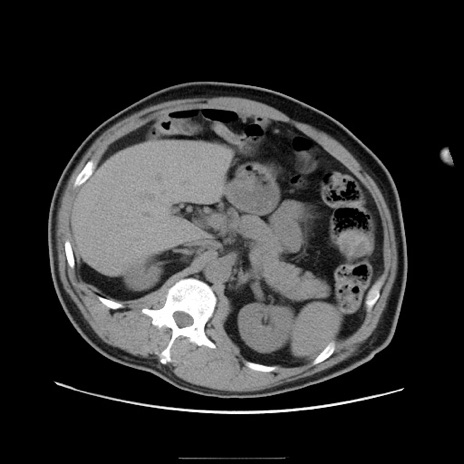

症例22(横断像)

【症例】50歳代男性

【主訴】腹痛

【現病歴】AVMからの被殻出血のため回復期リハ病棟入院中。 本日午後3時頃急に下腹部痛が出現した。

【既往歴】AVM、被殻出血、虫垂炎、高血圧

【身体所見】意識晴明、左半身不全麻痺、会話の理解は良好、36.5°C、腹部:膨隆、全体に板状硬、下腹部正中に圧痛点あり、反跳痛-、筋性防御不明、右下腹部にope scar

【データ】WBC 9400、CRP 0.06